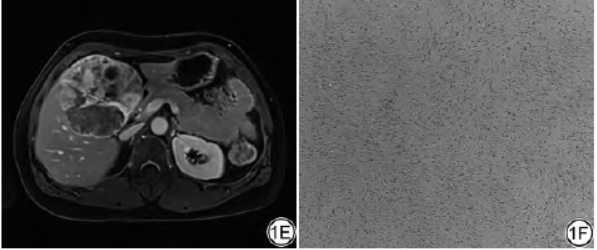

术中所见:切除部分肝组织,内见类圆形肿物,体积10.0cm×9.0cm×6.5cm,切面灰黄、灰白、质软,局部见囊腔,直径约1.4cm,肿物与肝被膜关系密切。免疫组化结果:Vimentin(+)、STAT6(+)、P16(弥漫+)、CD68(部分+)、SMA(部分+)、Bcl-2(部分+)、HMB45(少许+)、CD34(血管+)、CD31(血管+)、Desmin(个别+)、CD117(个别+)、CD23(-)、CD21(-)、CK广(-)、PR(-)、S-100(-)、Ki-67指数(2%)。病理结果:硬化性脂肪肉瘤(图1F)。

图1女,50岁,肝脏硬化性脂肪肉瘤。1A:T1WI病灶呈低信号;1B:T2WI压脂病灶呈高信号,内见分隔样低信号;1C:增强扫描动脉期可见斑片样、结节样强化;1D:门脉期强化范围增大;E:延迟期强化范围进一步增大,强化信号不均匀。1F:病理图,可见致密的胶原纤维化区域,梭形细胞有一定的异形性,核深染,不规则(HE×100)。